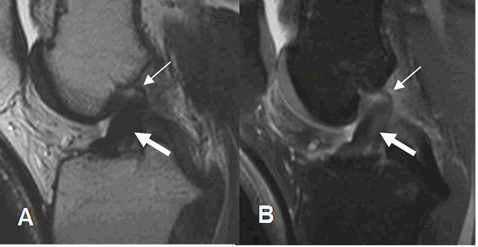

Fig 95 A. Ruptura aguda del LCA.

RM sagital en STIR. Clásica contusión del platillo tibial y el cóndilo femoral lateral, con depresión mayor de 1.5 mm (Flecha gruesa), constituyendo el signo de la muesca.